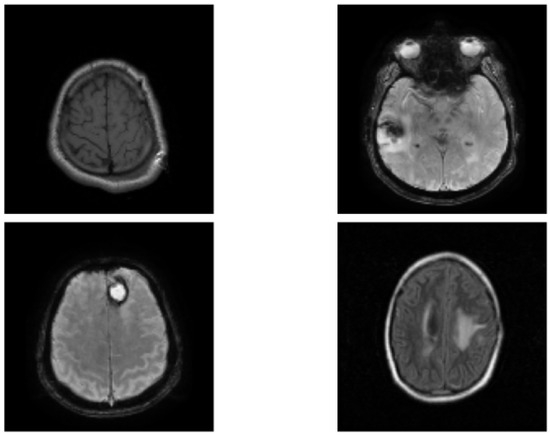

3.1. Dataset and Pre-Processing

3.4. Segmentation Network

4. Results and Discussion